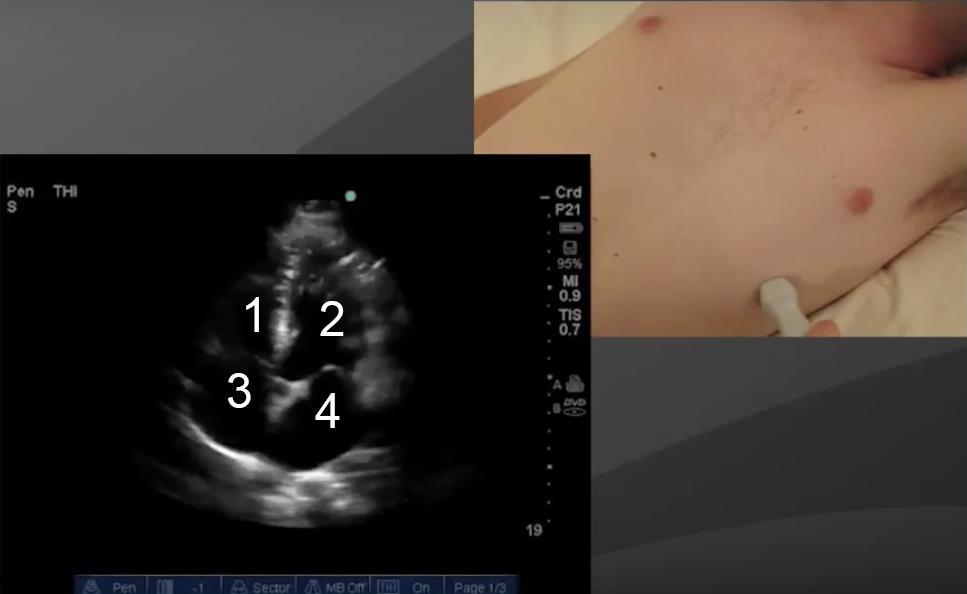

Heart Apical 4 Chamber View 2 Image

1. Right Ventricle (RV)

2. Left Ventricle (LV)

3. Right Atrium (RA)

4. Left Atrium (LA)